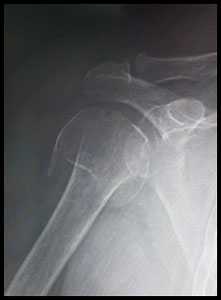

Рис. 1. На рентгенограммах: оскольчатый перелом проксимального отдела плечевой кости со смещением отломков.

рис. 1 а. рентгенограмма плечевого сустава - оскольчатый многофрагментарный перелом головки плечевой кости, б. на рентгенограммах плечевой сустав после эндопротезирования головки плечевой кости (гемипротез).